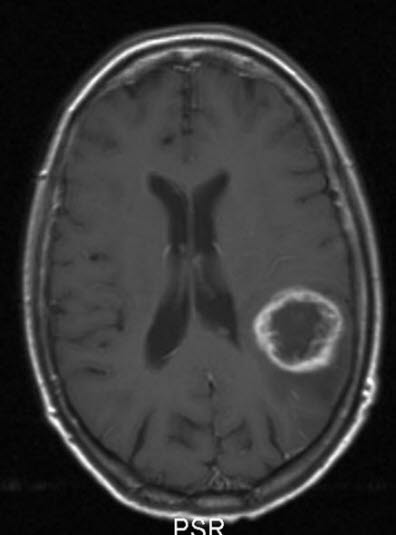

Glioblastom, aksialt snitt

Glioblastom WHO grad IV

Gjengitt med tillatelse av Radiologisk avdeling, Universitetssykehuset Nord-Norge